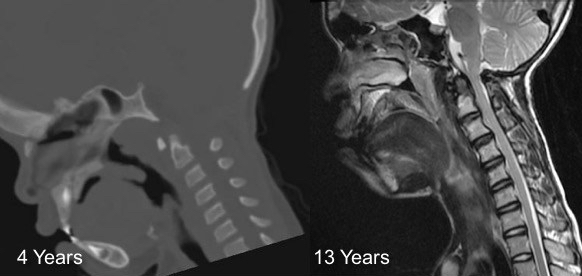

le canal cervical étroit de l’achondroplasie

il existe une étroitesse évolutive du canal cervical qui peut entraîner une compression médullaire et nécessiter une décompression par voie postérieure (laminoplastie). Cette compression se manifeste plus tard dans l’enfance et l’adolescence.

l’immobilisation post-opératoire est impérative en raison du risque de cyphose du fait du poids de la tête et de la laxité musculo-ligamentaire.